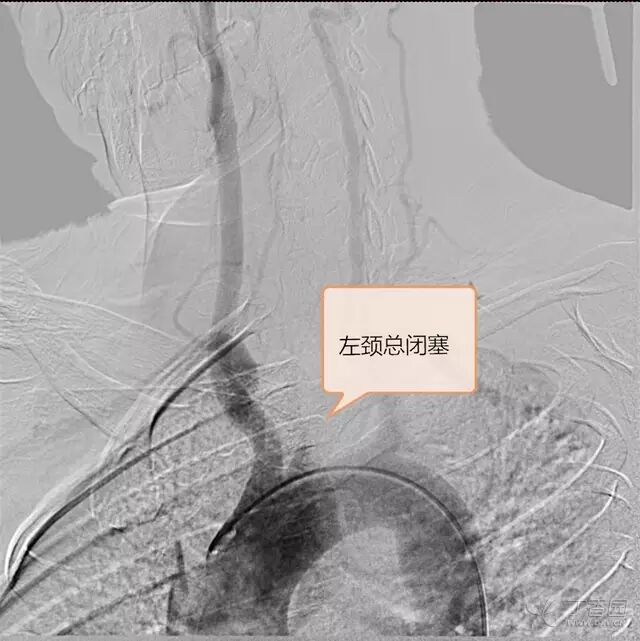

DSA:右锁骨下动脉起始部狭窄,狭窄率 96%,右椎动脉血流前向,右胚胎性大脑后动脉,左颈总动脉闭塞,左后交通动脉开放,后循环经左后交通动脉向左颈内动脉代偿,左甲颈干经左颈外动脉向左颈内动脉供血区代偿(图 1~4)。

图 1. 左侧颈总动脉闭塞